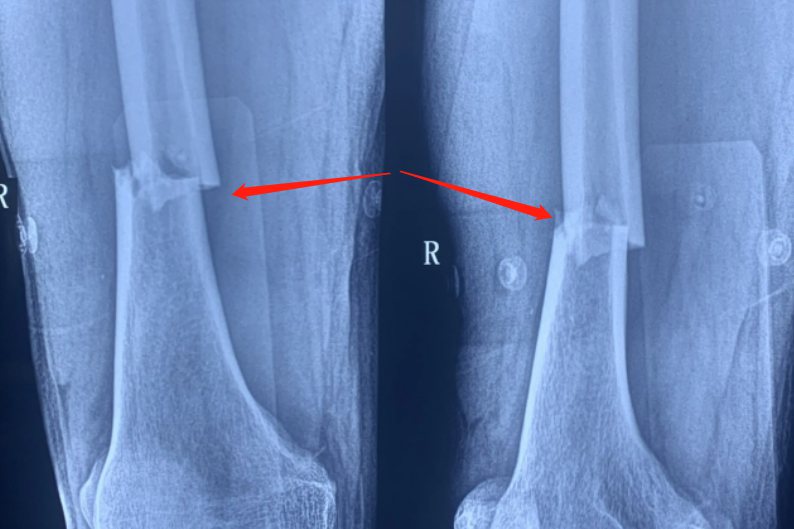

股骨干骨折:

股骨干骨折由于肌肉的牵拉作用骨折断端移位、成角明显,患肢出现短缩伴有明显的肿胀疼以及疼痛感觉。股骨干骨折出血量较大,患者容易出现头晕、面色苍白等休克表现。